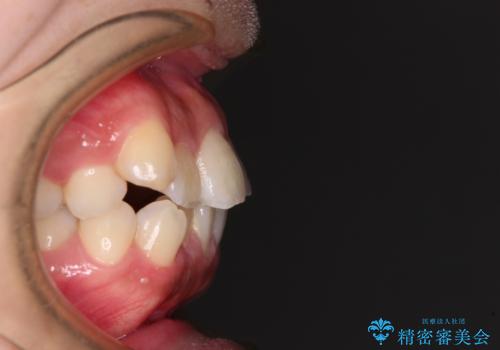

- 前歯の出っ歯と口元の閉じにくさを気にして来院された患者様です。

口元を積極的に引っ込めるために、上下左右の小臼歯4本を抜歯することとしました。

4本の歯を抜歯したことで、飛び出していた口元が引っ込み、横顔の印象が大きく改善されました。